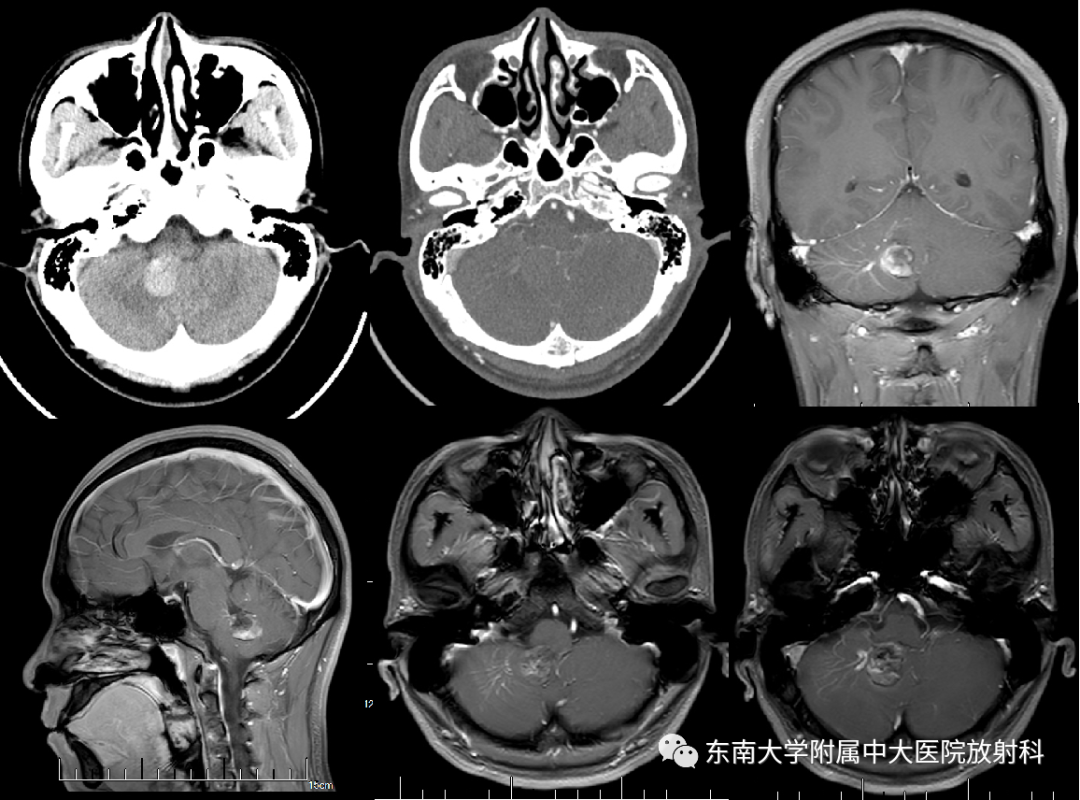

【PPT】颅内海绵状血管畸形

病史

男,26岁

主诉:头晕伴恶心呕吐、行走不稳5天

患者5天前无明显诱因下出现头晕,性质为持续性,伴有恶心呕吐、行走不稳,否认血性呕吐物